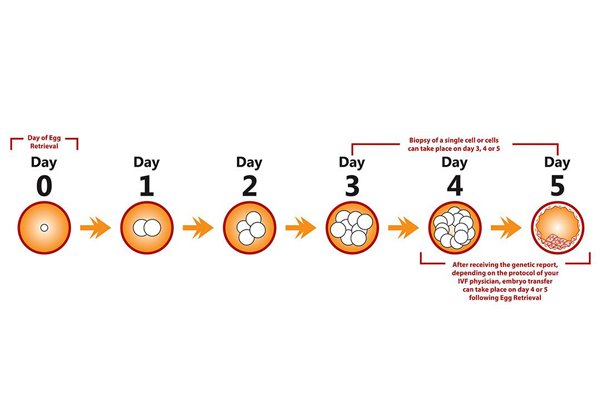

成功怀孕会经历以下几不同的阶段。- 精子必须到达并穿透并使女人的卵子受精。 - 产生的受精卵必须分裂并形成胚泡。 - 胚泡到达子宫并植入子宫内膜。 - 植入的胚泡...

试管婴儿精子和卵子结合形成受精卵,发育成胚胎,发育的胚胎需要在子宫内定居,胚胎着床需要多长时间?在卵子受精后,从输卵管到子宫需要几天的时间,胚胎继续生长和分裂,最...

胚胎培养技术是指在受精卵, 在体外条件下进行体外培养, 使其具有发育到2细胞胚胎乃至囊胚, 并具发育成一个孤立个体的潜能。传统的胚胎移植一般选择卵裂期胚胎但其多胎...

囊胚培养是精子与卵子结合为受精卵后继续在培养箱内培养5至6天,然后再进行移植或冷冻的方法。囊胚培养有哪些优点呢?能够筛选掉发育潜力差的胚胎早期的胚胎(受精后第二或...